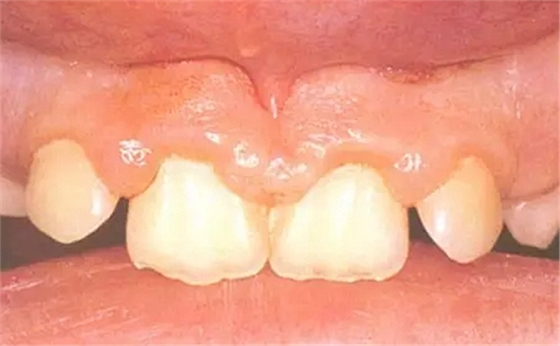

牙周組織疾病——不潔性齦炎

原因:3-5歲不刷牙,口腔衛(wèi)生差的兒童多見(jiàn);牙列擁擠、排列不齊或者戴用矯治器的兒童,自潔作用差,刷牙不到位時(shí)也可出現(xiàn)。

表現(xiàn):乳前牙和乳磨牙唇頰側(cè)較明顯。牙列不齊部位的齦緣和齦乳頭紅腫,易出血,局部有牙垢和食物殘?jiān)街?/p>